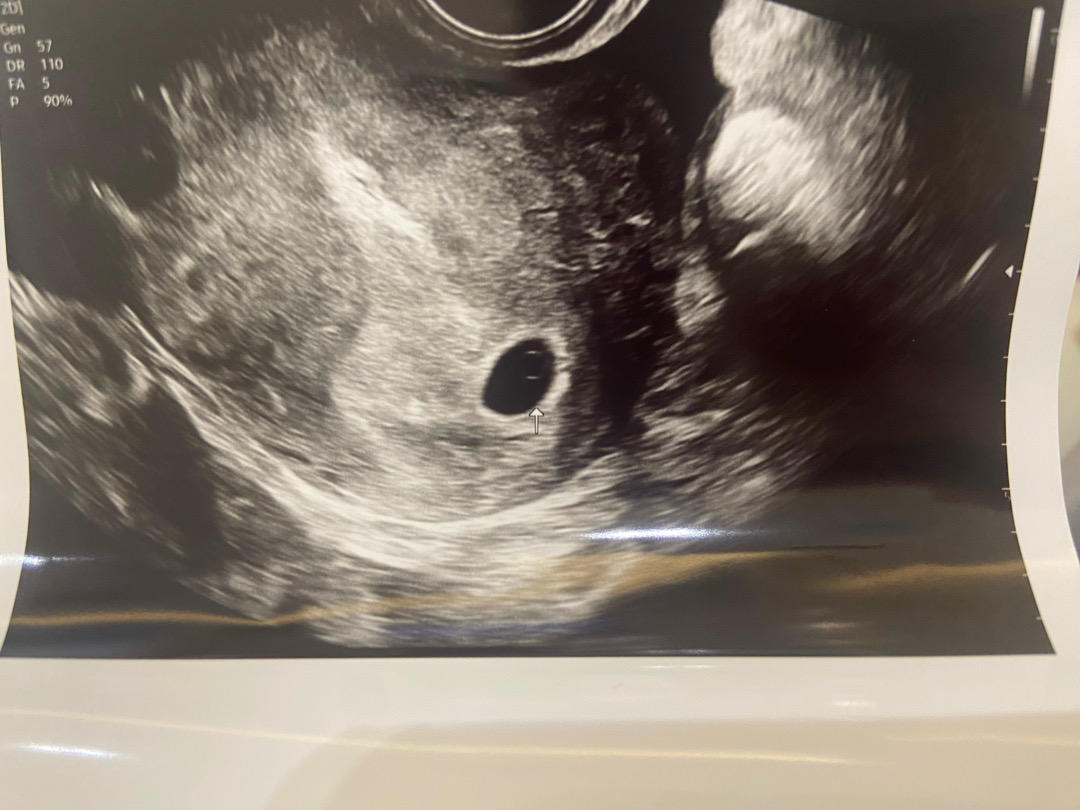

5주차 첫 초음파입니다

난황도 보이는 것 같네요!!! 축하드려용ㅎ

다음주 심장소리 들으러 오라고하시는데 떨리네요 하루하루가 팡파레입니다 :)